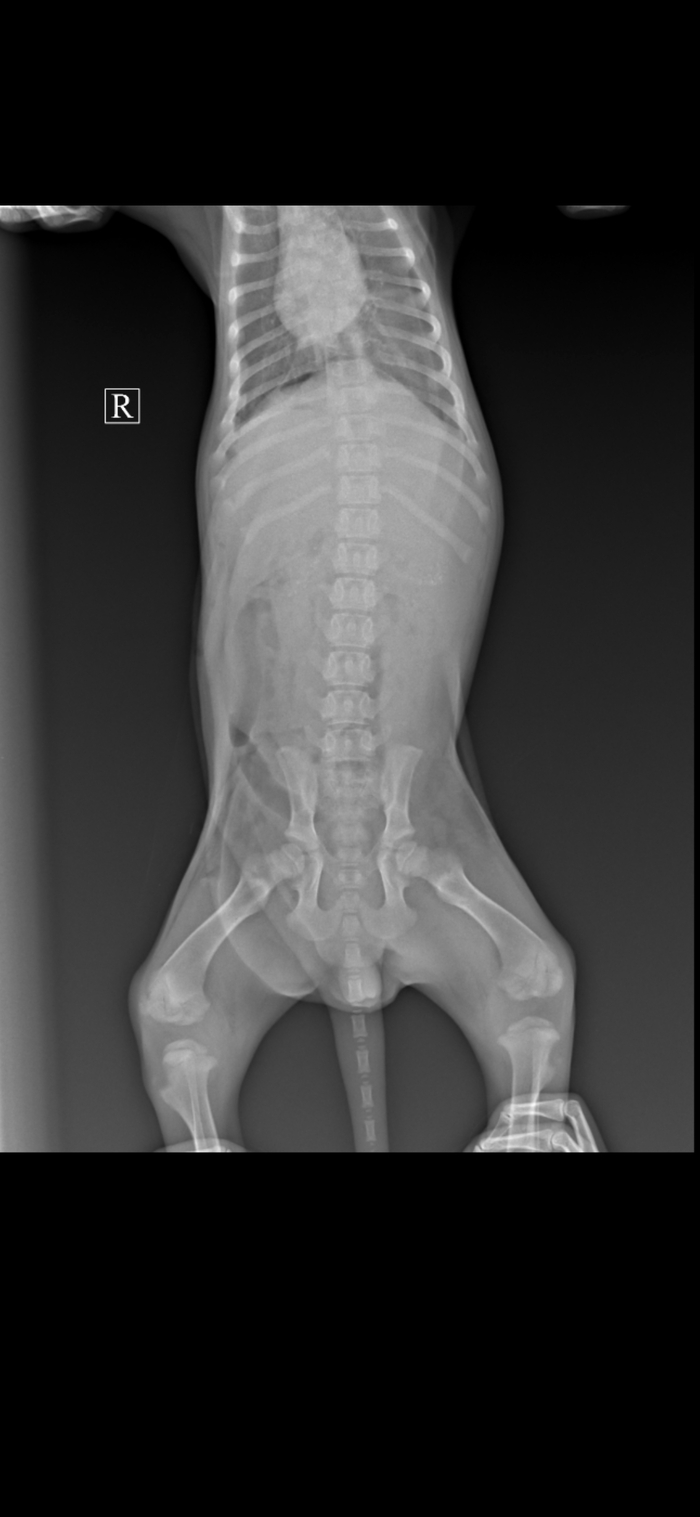

Сегодня Ржевский был на кастрации, сделал УЗИ и сдал анализы.

По УЗИ - острый холецистит и холангит. В мочевом пузыре большое скопление газа и взвеси.

По анализу мочи - присутствует кровь и запредельное количество белка.

Для установки диагноза, мочу отправили на бакпосев.

Так же сдали кровь на Лейкоз и Иммунодефицит. И Лейкоз РНК пришёл положительный.

Назначено: Урсофальк 1/4 капсулы 250 мг, 1 р/д на ночь. Курс 1 месяц.

Кладакса 250 мг 1/2т, 2 р/д или Амоксигард 0,5 мл п/к, 1 р/д. До готовности результатов бакпосева.

Масса 4,8 кг.